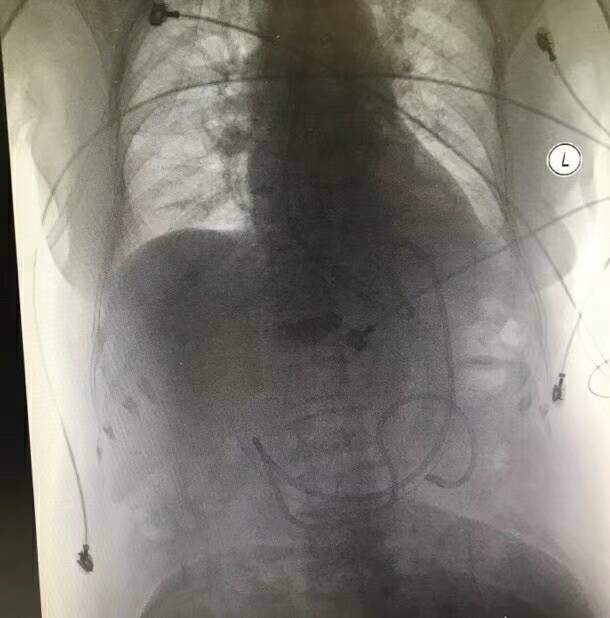

与经鼻胃管比较,鼻空肠管可避免肠内营养液对胃,十二指肠的刺激,使其保持静止修复状态,提高肠内营养的耐受性,改善营养状况,还能有效预防误吸,减少危重患者肠源性和多器官功能障碍综合征的发生,目前已成为危重症治疗的一项重要措施,并且主张尽早行空肠内营养, 我科于2017年10月成功开展了经鼻空肠管置入,经床旁X线确认位置正确!